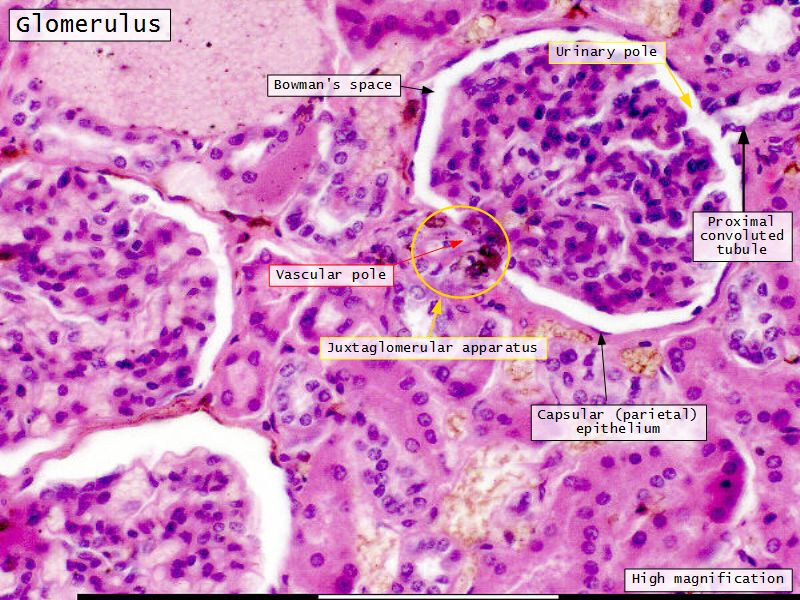

Renal corpuscle

- Two sides

- Vascular pole

- Tubular pole

Epithelium layers

- Capillary endothelium

- Visceral layer of epithelium

- Podocytes

- Resting on glomerular basement membrane

- Capsular space

- Parietal layer of epithelium

- Simple squamous epithelium

Juxtaglomerular complex

Area where distal convoluted tubule return to glomerulus and pass through the notch between the afferent and efferent arterioles. Modification of the wall of the tubule and afferent arteriole and presence of specialised cells in the connective tissue.Modifications

- Distal convoluted tubule

- Macula densa

- Narrow epithelial cells

- Nuclei densely packed

- CT cells

- Laci cells

- Similar to mesangial cells

- Afferent arteriole

- Modified smooth muscle cells

- Juxtaglomerular cells

- Secretory function

Capillaries

- Supported by

- Mesangial cells

- Mesangial matrix

- Phagocytic

- Maintain basement membrane

- Remove macromolecular deposits

Proximal convoluted segment

- Longest part of nephron

- Wide triangular cell

- Spherical nucleus

- Indistinct cell borders

- Luminal surface

- Striated brush border